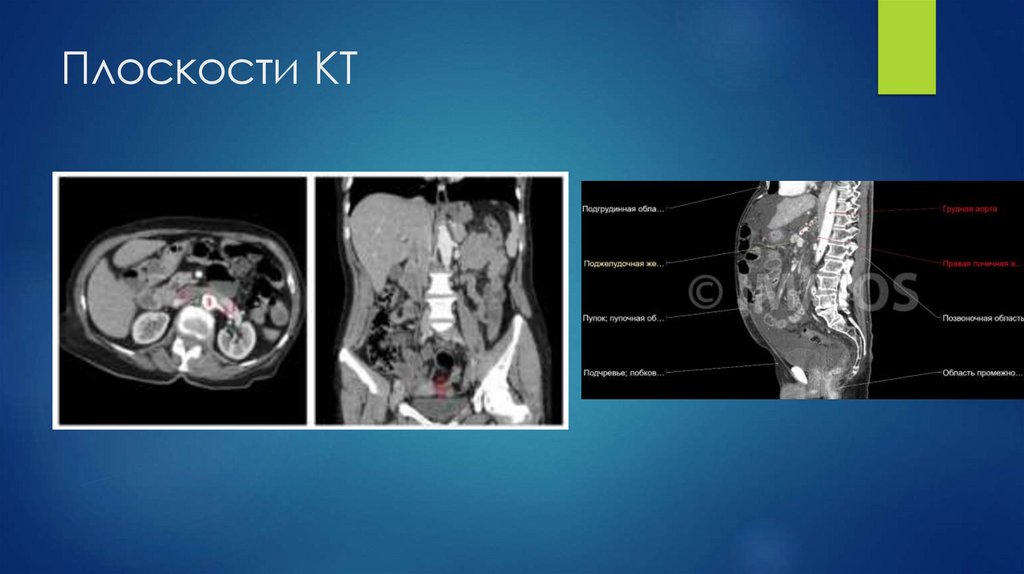

Плоскости КТ

65. Плоскости КТ

66. Плоскости КТ